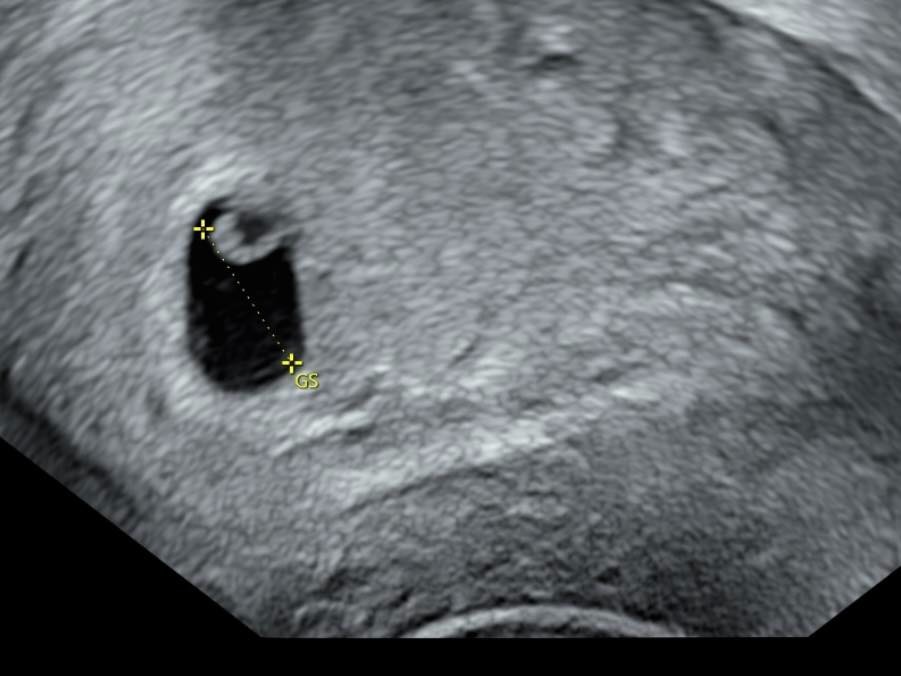

鄭家純提到,她懷孕9週,昨天確認胚胎停止發育得終止妊娠。半個月前產檢發現胚囊發育晚了一週。醫生說有兩個可能,一個是排卵期晚一週,另一個可能就是胚胎有狀況,下次產檢若沒有照到心跳就是確定停止發育,需安排終止妊娠。

鄭家純指出,昨天傍晚就開始少量出血,2小時後出血量變多開始腹痛,立刻去急診,在醫院時陸續有排出血塊,照了陰道超音波確認胎囊大小與半個月前產檢時一樣,目前的處置就是回家休息吃止痛藥,等體力恢復後回台灣做後續。